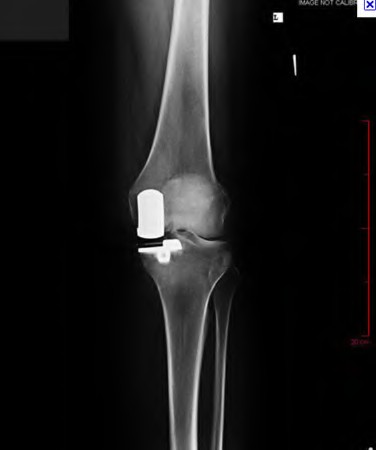

Question 18:

During a primary total knee arthroplasty (TKA), the surgeon evaluates the flexion and extension gaps. Utilizing spacer blocks, the surgeon notes that the extension gap is symmetric and perfectly balanced, but the flexion gap is excessively tight. Assuming an anterior referencing sizing guide was used, which of the following surgical adjustments is the most appropriate next step to balance the knee?

Correct Answer: Downsize the femoral component

Explanation:

When using an anterior referencing system, the anterior flange of all femoral components rests on the same cut surface. Downsizing the femoral component reduces its anteroposterior dimension by removing more bone from the posterior condyles. This specifically enlarges the flexion gap without altering the extension gap, thereby resolving an isolated tight flexion gap.